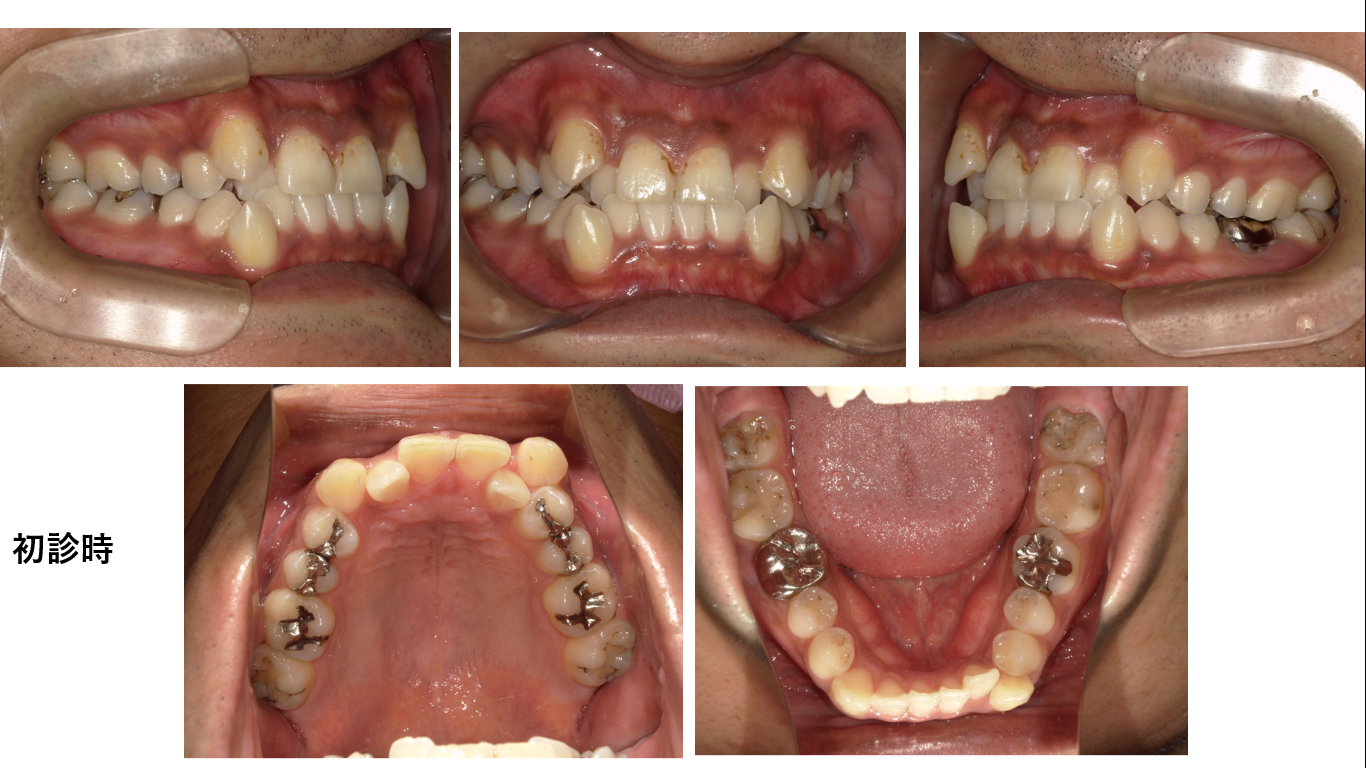

初診時34歳男性、治療期間3年4か月、抜歯部位:上顎週左右4番、下顎右側4番、下顎左側6番、8番。治療費総額124万円(税込み)左の6番は根幹治療がしてあり根尖病巣を確認できたので抜歯となりました。下...